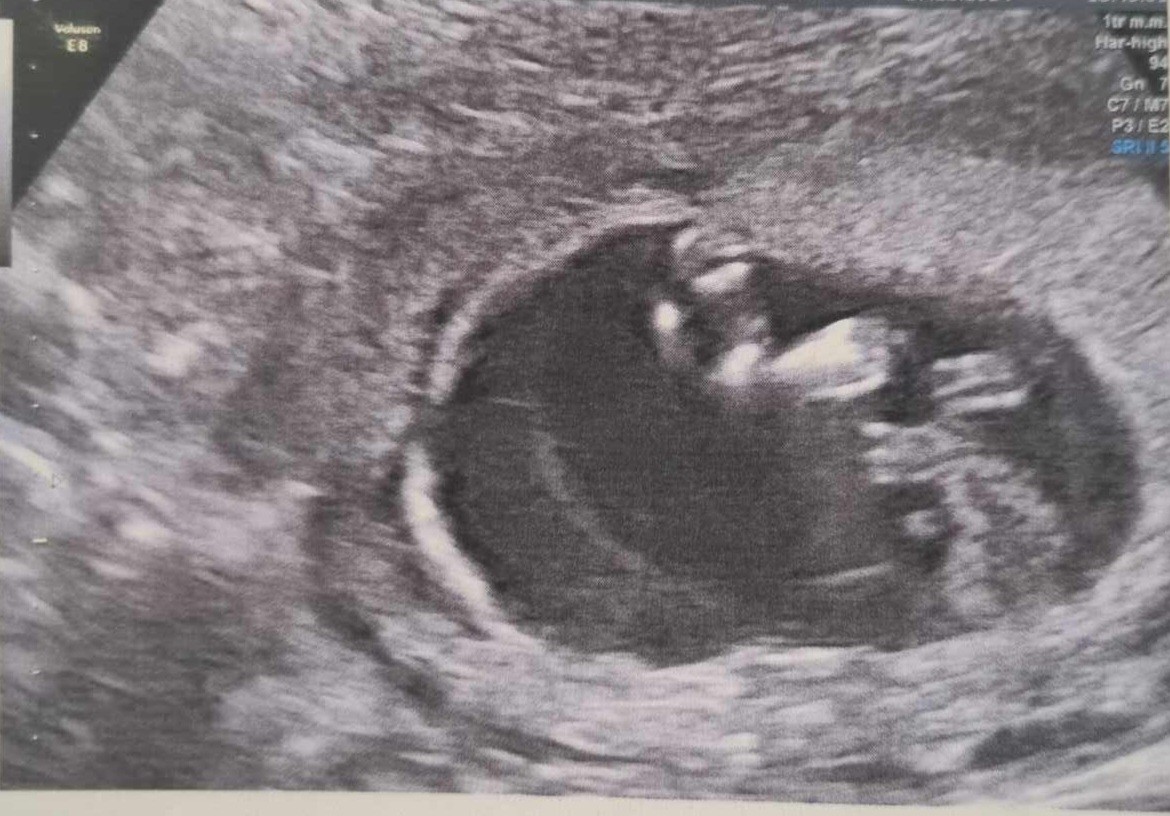

Cześć dziewczyny, zaczynam dzisiaj 17 tydzień. Wczoraj mialam usg i nadal nie znamy płci :( Czy możecie pomóc? :) Co myślicie po zdjęciach z badań prenatalnych? :) Na badaniach dowiedzieliśmy, że płeć do potwierdzenia na kolejnych :/

Z zamieszczonych zdjęć niestety nie da się ocenić, ale jak bardzo wam zależy na szybkim poznaniu płci to polecam NIFTY lub saco, można poznać już nawet w 10 tygodniu.

A na zdjęciach niestety ale faktycznie nie da się w 100% określić płci. Bywa i tak.